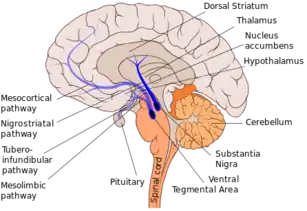

Dopamine

Dopamine, a neurotransmitter, has been linked with feeding behaviors. In an experiment, scientists measured how much food and water mice consumed when they were born without dopamine in their systems. They found that without dopamine, the mice would starve and be dehydrated to the point of death. The scientists then injected the mice without dopamine with its precursor, L-DOPA, and the mice started eating again. But, even though the mice were born without dopamine in their systems, they still had the capacity to control their feeding and drinking behaviors, suggesting that dopamine does not play a role in developing those neural circuits. Instead, dopamine is more closely related to the drive for hunger and thirst. Although the lack of dopamine resulted in adipsia in these rats, low levels of dopamine do not necessarily cause adipsia. [9]

Other findings in support of the role of dopamine in thirst regulation involved the nigrostriatal pathway. After completely degenerating the pathway, the animal becomes adipsic, aphagic, and loses its interest in exploring. Although dopamine plays a role in adipsia, there is no research involving exclusively the relationship between adipsia and dopamine, as changes in dopamine simultaneously mediate changes in eating and curiosity, in addition to thirst.[10]